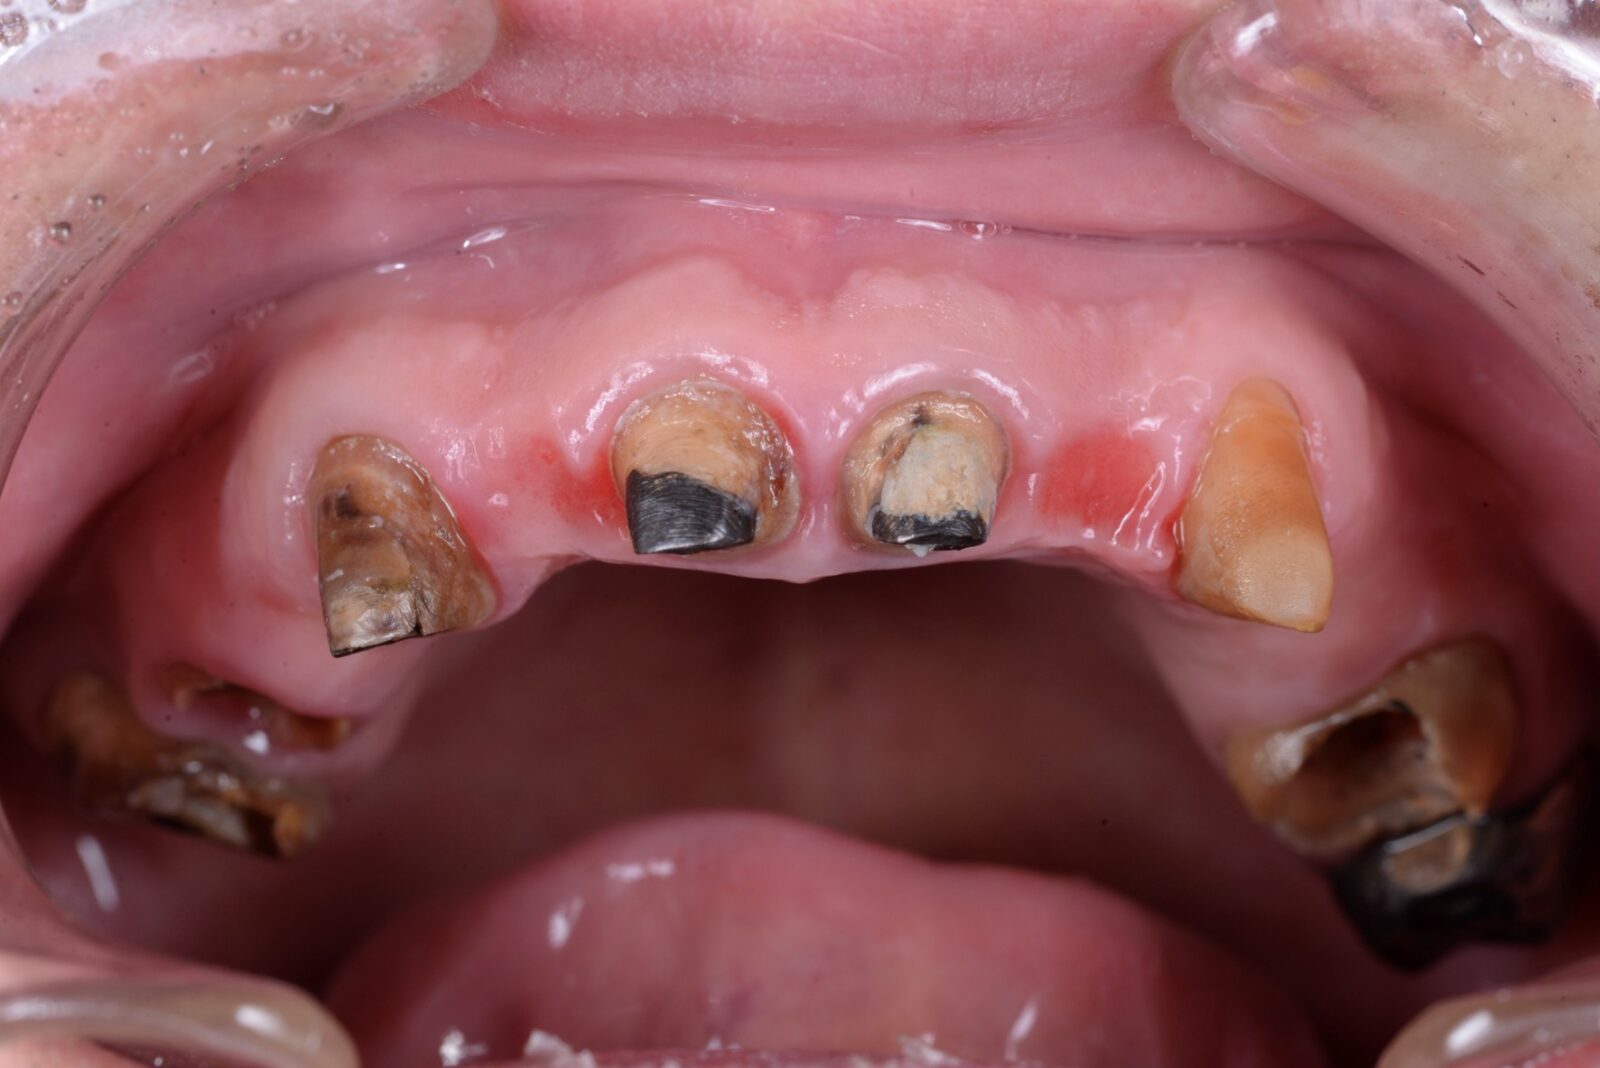

歯がボロボロになるまで

行けなかった理由

• 治療前

• 治療後

ボロボロの歯でも大丈夫。まずはお話から

歯の状態が悪くなると、見た目だけでなく、日常生活そのものに影響が出てしまうことがあります。実際に、当院には次のようなお悩みを抱えて来院される方が少なくありません。